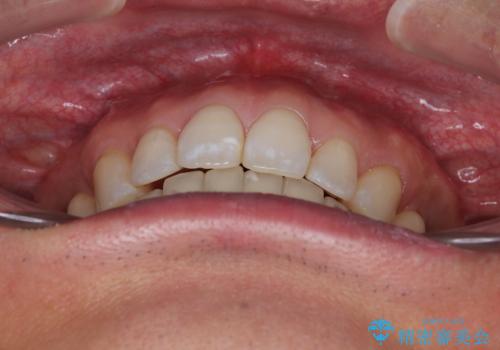

- 口元の突出感を気にして来院された患者様です。

強い咬合力と上顎前歯の傾斜により前歯が突出し、唇が閉じにくい状況であったため、上下左右の第一小臼歯4本を抜歯し、ワイヤー装置にて矯正治療を行うこととしました。

非常に咬合力が強いため、抜歯したスペースが閉じるのか不安でしたが、順調に歯が移動し、予定よりも早く治療を終えることができました。